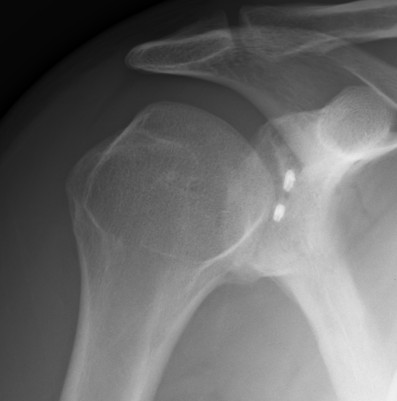

Case 1

Recurrence of instability without trauma

- anchors very high

- into glenoid face

- MRI suggests remaining inferior bankart

- no bony deficiency, no HAGL